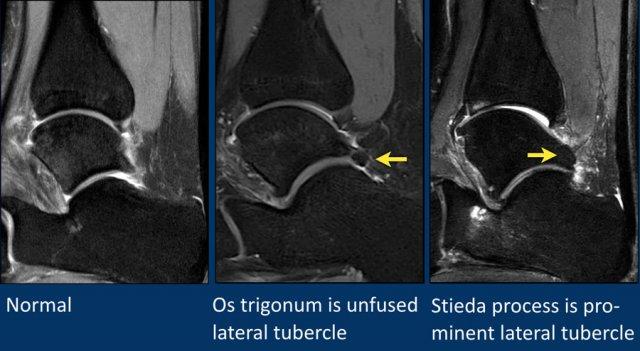

Os Trigonum

Ở bàn chân và cổ chân, có thể thấy nhiều xương phụ (accessory ossicles) khác nhau.

Xương phụ phổ biến nhất là os trigonum, là một mấu xương (apophysis) nổi bật chưa hợp nhất của củ bên (lateral tubercle) xương sên.

Os trigonum hiện diện trong dân số bình thường với tỷ lệ khoảng 5-15%.

Sự chèn ép os trigonum và các mô mềm xung quanh giữa xương chày và xương gót trong động tác gấp lòng bàn chân (plantar flexion) có thể là nguyên nhân gây hội chứng chèn ép phía sau (posterior impingement).

Điều này đặc biệt hay gặp ở các vũ công ballet.

Thuật ngữ “mỏm Stieda” (Stieda process) được dùng khi củ bên xương sên rất nổi bật.

Điều này cũng có thể dẫn đến hội chứng chèn ép phía sau.